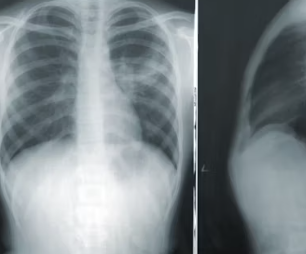

근골격계 문제

오른쪽 갈비뼈 아래 통증이 반드시 내부 장기 문제만은 아닙니다. 갈비뼈 자체의 염증이나 주변 근육의 문제로도 통증이 발생할 수 있습니다. 늑연골염(갈비뼈와 흉골을 잇는 연골에 염증이 생기는 것)은 가슴 통증을 유발하며, 오른쪽 갈비뼈 부위에서도 나타날 수 있습니다.

또한, 무리한 운동이나 갑작스러운 움직임으로 인한 근육통, 갈비뼈 골절 또는 금이 간 경우에도 통증이 발생할 수 있습니다. 이러한 통증은 특정 자세를 취하거나 움직일 때, 혹은 해당 부위를 눌렀을 때 더욱 심해지는 경향이 있습니다. 휴식이나 온찜질 등으로 완화될 수 있습니다.